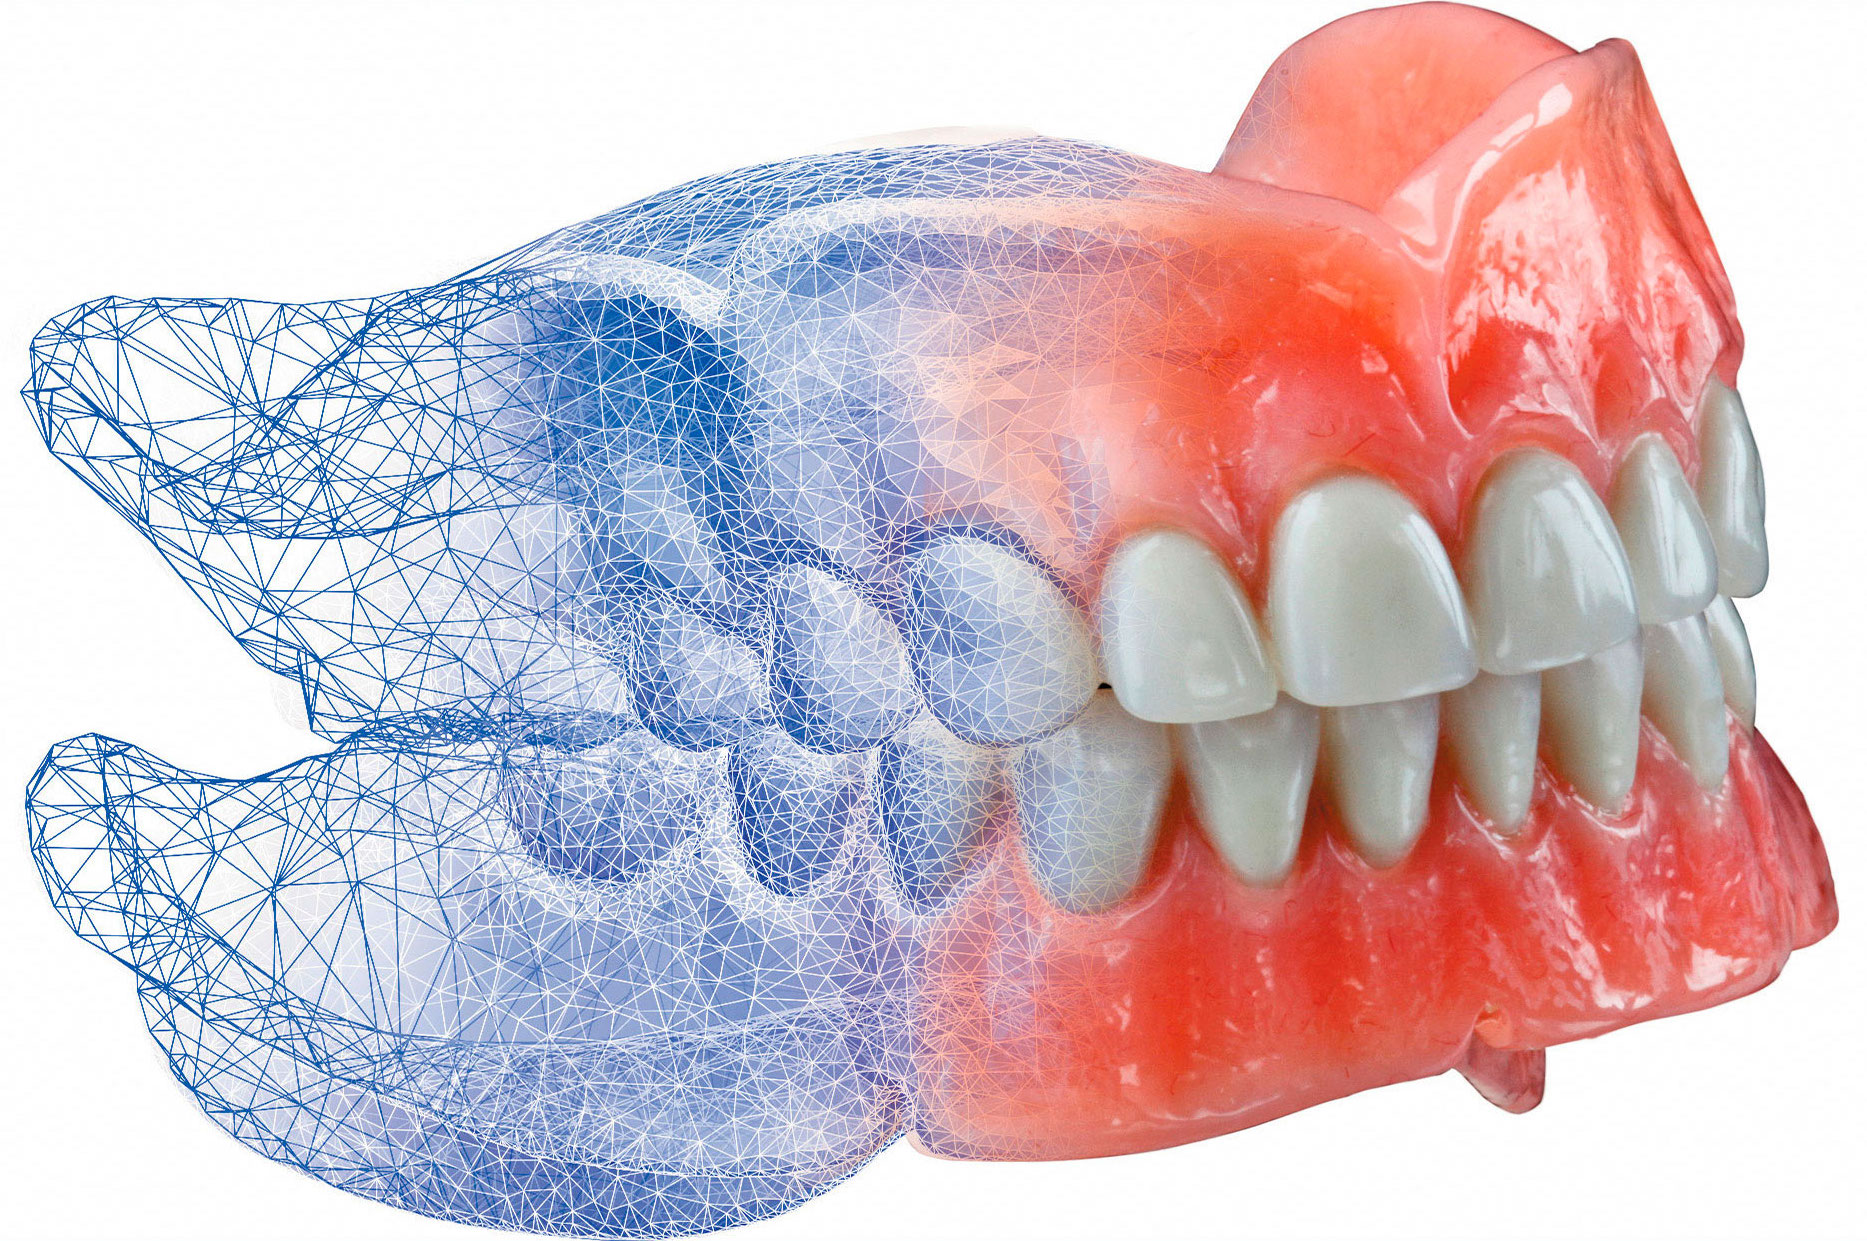

Протезирование: когда это единственный выход?

Протезирование используется в случаях, когда сохранить зуб невозможно или оно экономически нецелесообразно. Основные ситуации:

- Наличие дефектов вследствие удаления зубов или их утраты, требующих установки мостов, имплантатов или съемных протезов.

Плюсы и минусы протезирования

Преимущества:

- Быстрый результат — восстановление функции и эстетики за короткое время.

- Возможность восстановления даже при полном отсутствии зубов.

- Разнообразие методов: мосты, импланты, съемные протезы — выбор зависит от ситуации и бюджета.